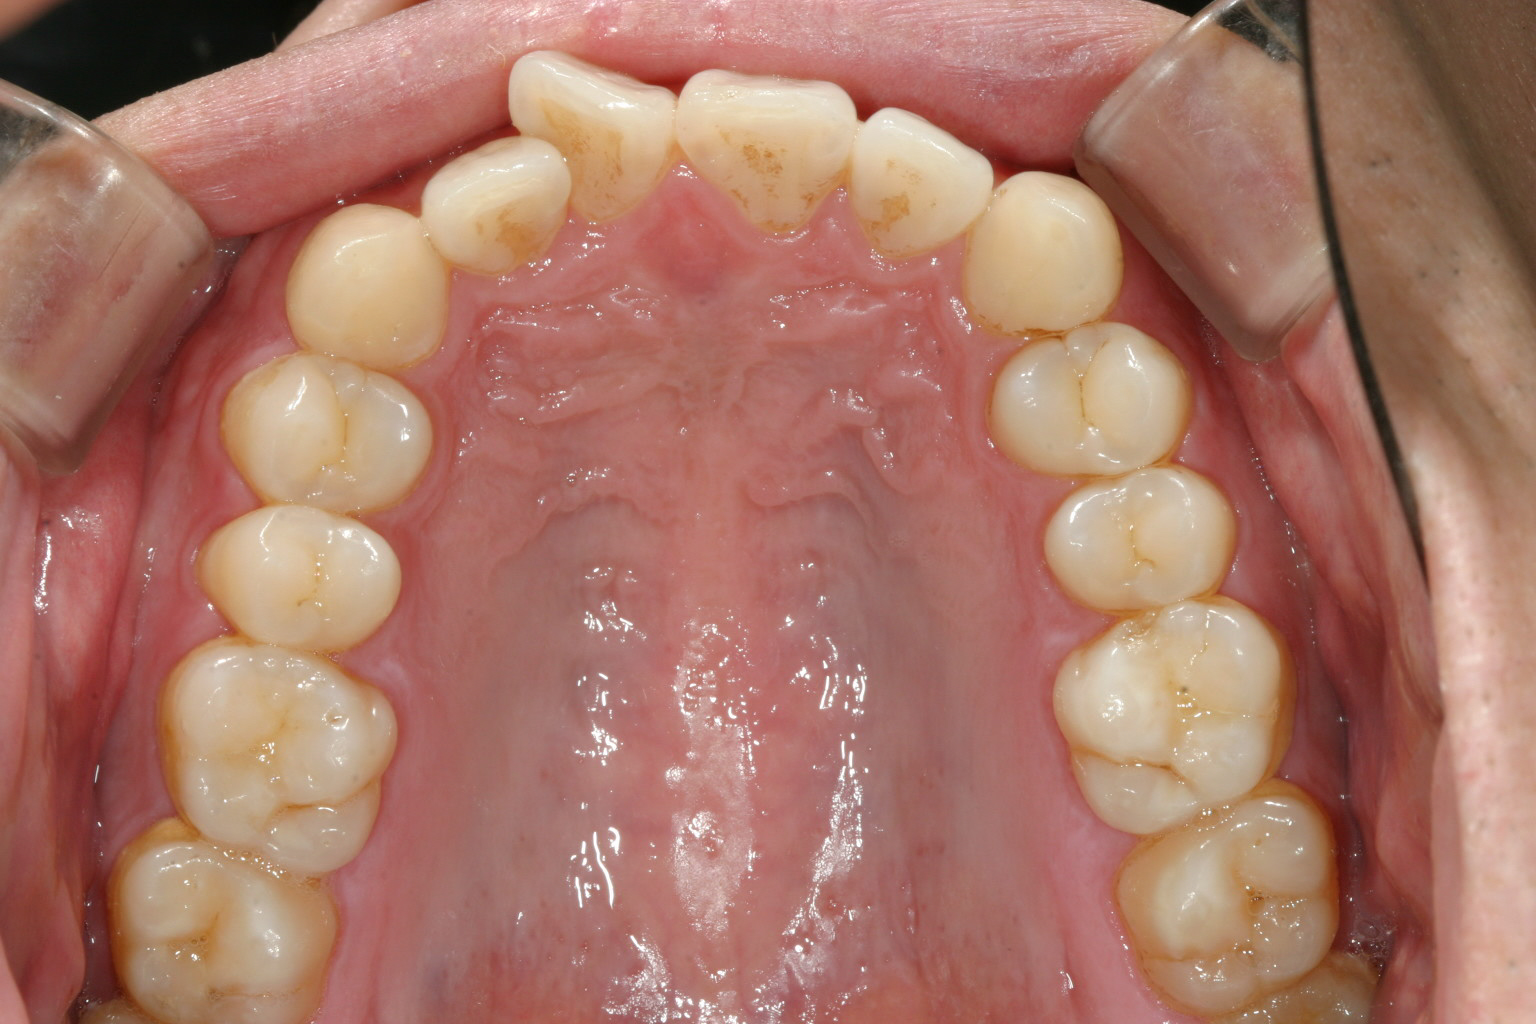

右上の前歯が少し捻転しています。

捻転歯が有る為に少し前突感があります。